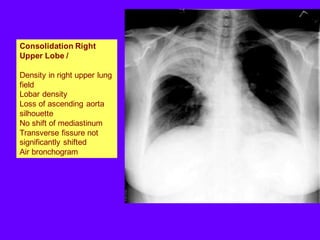

Consolidation Right

Upper Lobe /

Density in right upper lung

field

Lobar density

Loss of ascending aorta

silhouette

No shift of mediastinum

Transverse fissure not

significantly shifted

Air bronchogram